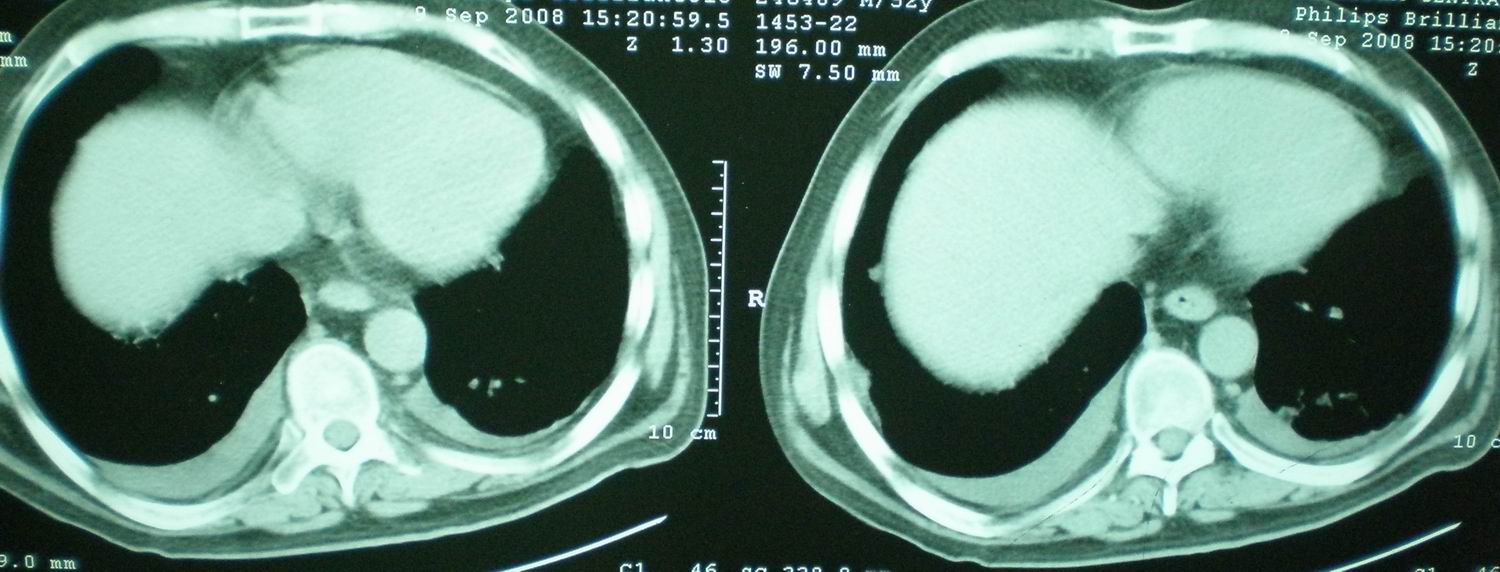

2008年11月18日今天的ct片

[face=宋体]显然上级医院进行了抗结核,抗真菌,抗炎等治疗,目前病人肺内病灶基本消失,双侧胸腔积液,右侧积液量有吸收,抗结核一个多月,现在病人疑问,结核的诊断是否有疑义,抗结核是否继续,因为那个毕竟副作用大。[/face]

我仔细看了下病人的出院小结,当时情况危急,诊断里有1型呼衰。心包周围的是脂肪密度。结合三次ct扫描的图象分析,个人认为:1、病人目前肺部病灶基本消失,双侧胸腔内少量积液,抗结核治疗才一个多月,就算是结核,抗结核治疗有效果,为何效果如此好,一点纤维灶的痕迹都没有呢,再就是患者做过气管镜检查及活检、痰检均未找到结核的证据。所以不支持结核的诊断。

2、结合现在的ct片,考虑:肺水肿及真菌感染,双侧胸腔积液。